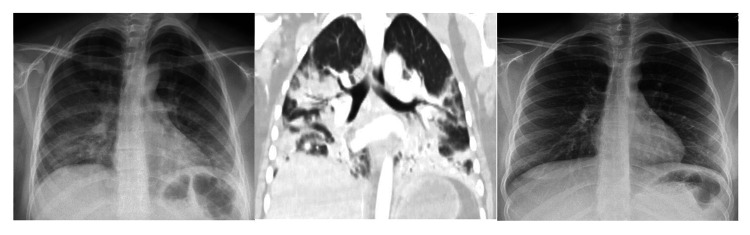

A 19-year-old female with a medical history of seizures and neurocysticercosis status post-stereotactic brain biopsy that was treated in her childhood presented with a complaint of worsening shortness of breath. She endorsed vaping for about two years and denied any drug use. She did not take any medication. Family history and environmental exposure were unremarkable. She had a recent emergency room visit for abdominal pain associated with nausea and vomiting a week prior to admission. On presentation, she was afebrile, with a heart rate of 134 beats per minute, respiratory rate of 16 breaths per minute, and blood pressure of 121/68 mmHg. Scattered end-expiratory wheezing and mild diffuse rhonchi were noted on auscultation. She denied any sick contacts. Chest X-ray demonstrated multifocal bilateral opacities (Figure 1), and labs were remarkable for a white blood cell (WBC) count of 13.8 K/µL. Rapid influenza was negative. She was empirically started on ceftriaxone and azithromycin for community-acquired pneumonia (CAP). Hypoxemia progressed and she required intubation, followed by mechanical ventilation. An echocardiogram revealed a normal left ventricular ejection fraction of 65-70%. Multiple blood cultures, sputum, and tracheal aspirate cultures, as well as a workup for atypical infections, including fungal and mycobacterial infections, were all negative. Human immunodeficiency virus (HIV) and immunoglobulin levels were unremarkable, and there was no evidence of an immunocompromised status. Vasculitis and connective tissue disease workup were negative as well. The patient underwent bronchoscopy with bronchoalveolar lavage (BAL) which showed only neutrophilic alveolitis (BAL had 1,075 red blood cells (RBCs) and 557 WBCs with a differential of 53% neutrophils, 35% monocytes, 10% lymphocytes, and 2% eosinophils). A surgical lung biopsy of the left lower lobe was performed. She finished a seven-day course of antibiotics (cefepime, levofloxacin, and linezolid) and was extubated two days after the open lung biopsy that revealed diffuse interstitial fibrosis associated with type 2 pneumocyte hyperplasia and patchy organizing pneumonia suggestive of acute lung injury and nonspecific interstitial pneumonia (NSIP) (Figure 2). NSIP can be one of the outcomes of acute lung injury.

An 18-year-old woman with a medical history of obsessive-compulsive disorder and exercise-induced asthma presented with complaints of chest tightness and shortness of breath. The patient endorsed vaping and using marijuana daily for two years prior to admission. Vital signs on presentation included heart rate of 120 beats per minute, respiratory rate of 24 breaths per minute, and oxygen saturation of 93% on room air. Lung sounds were clear to auscultation. WBC count was 19.4 K/µL. CT chest showed patchy bilateral airspace GGOs (Figure 4) and no evidence of pulmonary embolism.